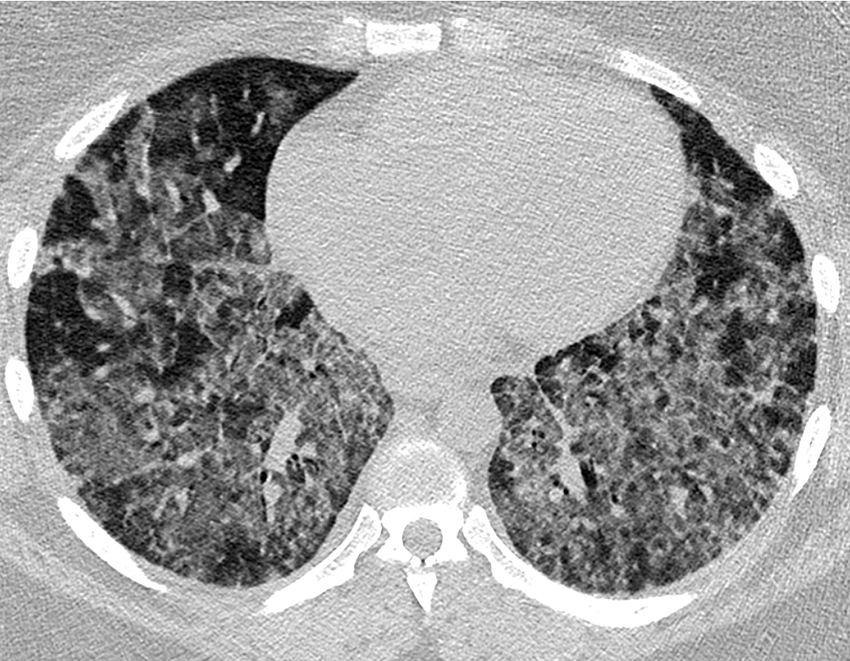

Bildet viser lungeparenkymet hos en tidligere frisk kvinne i begynnelsen av 30-årene, gravid med tvillinger. CT aksialsnitt i lungevindu gjennom lingula og underlapper viser utbredte mattglassfortetninger og fortykkede interlobulære septa.

Pasienten ble innlagt i medisinsk avdeling ved lokalsykehus etter en kortvarig sykehistorie med økende dyspné og respirasjonsavhengige brystsmerter. Ved innkomst ble det avdekket respirasjonssvikt uten hyperkapni, med PaO2 8,8 kPa, og grov jernmangelanemi (Hb 6,6 g/dl). Lungeembolisme og infeksjon ble avkreftet. Det ble ikke påvist patologi hos fostrene. Bildefunn ga mistanke om alveolære blødninger, og pasienten ble overført til lungeavdelingen ved Rikshospitalet. Ved bronkoalveolær lavage ble det påvist lett blodtilblandet skyllevæske. Etter tverrfaglig vurdering fant man ingen holdepunkter for underliggende tilstander som blant annet autoimmun sykdom. Det kliniske bildet var forenelig med jernmangelanemi som følge av idiopatisk pulmonal hemosiderose. Hun fikk jerntilskudd og høydosebehandling med kortikosteroider, med overgang til peroral behandling i nedtrappingsregime. Dette ga god klinisk og radiologisk respons.

Sykdomsforløpet er uforutsigbart og kan veksle mellom akutt og kronisk fase (2). Den klassiske triaden i en akuttfase består av hemoptyse, jernmangelanemi og lungefortetninger på CT. Den kroniske fasen kan bestå av symptomer relatert til progredierende lungefibrose som utvikles hos enkelte som følge av akkumulering av hemosiderin i lungene (2). Noen av pasientene har imidlertid lange remisjonsperioder med sparsomme symptomer (1).